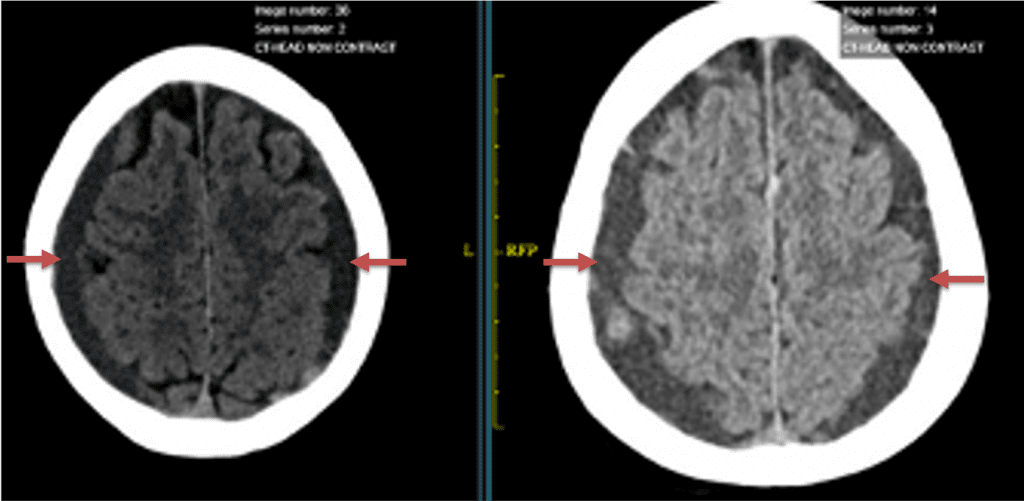

CT follow-up at 1 week demonstrates early resorption. 2 weeks post MMA embolization, resolution of the left subdural collection with new small thin acute hemorrhage in an otherwise stable right subdural collection is observed (Figure 3. A and B).

Figure 3. A) 1 week post MMA embolization demonstrating decreasing thickness bilaterally B) 2 weeks post MMA demonstrates resolution on left, with small new acute component on right with overall decreased thickness.

Clinically, the patient improved over the few weeks with the occasional transient twinge of a headache, but resolution of dizziness. Follow-up CT at 10 weeks demonstrated complete resolution of the bilateral subdural hematomas with our patient completely asymptomatic and back to all of her activities of daily living. Considering her history of thrombocytopenia and CLL, we will continue to monitor her into the future and are excited about her progress and recovery. (Figure 4. A and B)

Figure 4. A and B) – 10 weeks following embolization demonstrates complete resolution of bilateral collections both acute and chronic.